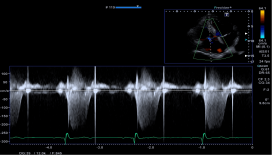

10. 全面的心脏应用:Aplioi900可为临床提供全方位心脏超声解决方案,支持专业的经胸心脏探头及经食道探头。

1) 二维/三维室壁运动追踪技术 (2D/3D Wall Motion Tracking)

2) 心脏容积成像